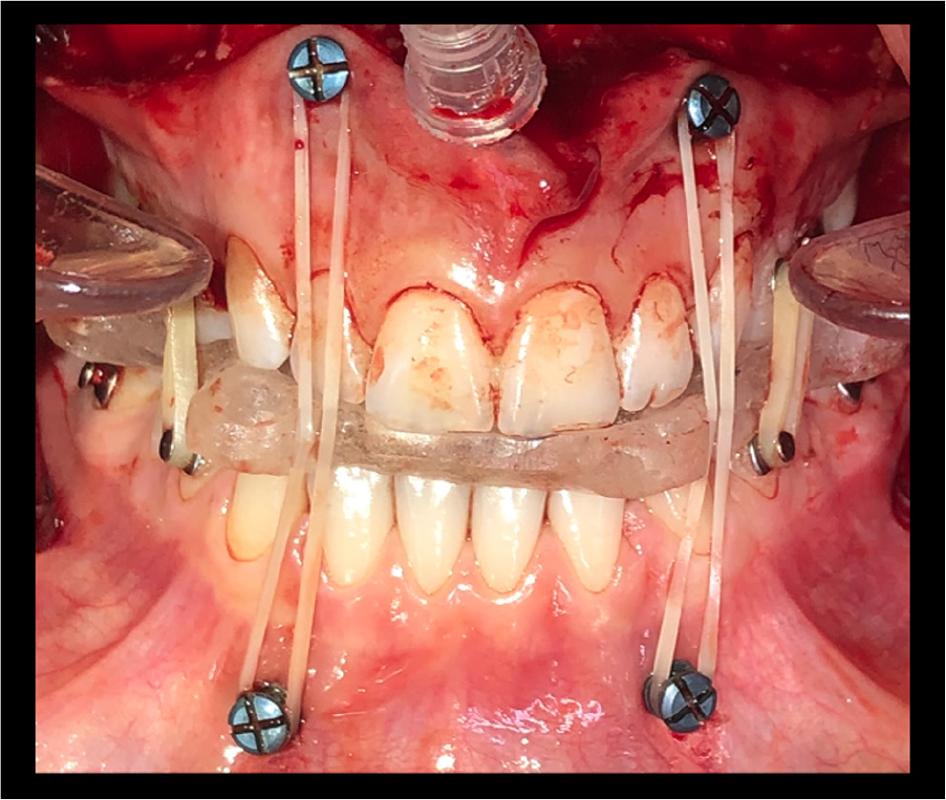

Figure 6

Intra-operative photographs showing the intermaxillary fixation with mini-screws.

Dolphin Imaging software (Version 11.5 Premium, Chatsworth, CA, USA) was used to plan surgery and soft tissue simulation was performed accordingly (Fig. 5). The patient did not have a gummy-smile, therefore, a surgical plan was prepared in which the amount of impaction would not be excessive. The surgical plan consisted of a Le Fort 1 osteotomy involving a 4-mm advancement and 2-mm impaction of the maxilla, a mandibular setback of 4-mm via a bilateral sagittal split ramus osteotomy plus a reduction genioplasty of 2 mm. The surgical splints were constructed and the surgery was performed according to the surgical plan. During the procedure, in addition to the labial buttons bonded to the teeth, four mini-screws (diameter, 2 mm; length, upper 12 mm, lower 10 mm; KLS Martin, Umkirch, Germany) were inserted in each quadrant to support surgical intermaxillary fixation (Fig. 6). After the rigid internal fixation of the bone segments was established, the mini-screws were immediately removed. The second splint was removed after the surgery and light intermaxillary elastics were applied during the recovery period. The patient was discharged from hospital two days later without sign of complications.

The method of surgical intermaxillary fixation is critical in orthognathic surgery. In SFA studies, investigators have attached a single bracket or an arch wire directly to the teeth for intermaxillary fixation.1,10 However, in lingual surgery cases, temporary anchorage devices are considered mandatory because the lingual appliances cannot be used for the application of intermaxillary fixation.28 Temporary anchorage devices allow a large range and magnitude of orthodontic vectors and avoid premature contacts.9,18 One of the authors of the present report (ÖPÖ) trialed various intermaxillary fixation techniques for lingual orthodontics and recommended the use of labial buttons and mini-screws for the best surgical outcome. In the present case, four mini-screws were used for intermaxillary fixation and were removed immediately after rigid internal fixation of the bone segments was no longer required.